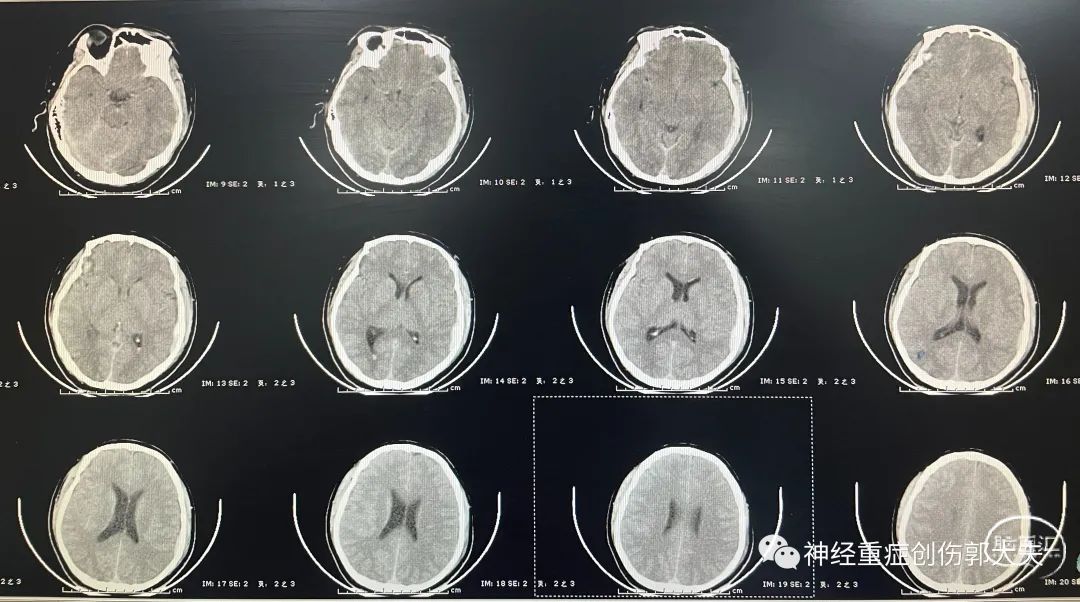

患者男性,36岁,主因“高处坠落致头部外伤1天”入院,神志浅昏迷,GCS9分,头颅CT显示右额叶脑挫裂伤,左颞叶急性硬膜下血肿,蛛网膜下腔出血。

患者颅内血肿量并不大,但是GCS评分低,根据颅内压监测共识,给予置入脑室型颅内压探头。术中初压32mmHg,经过缓慢释放少量脑脊液后下降为17mmHg。术后返回神经外科ICU,复查移动CT显示探头位置位于侧脑室内,ICP波动于10-20mmHg。